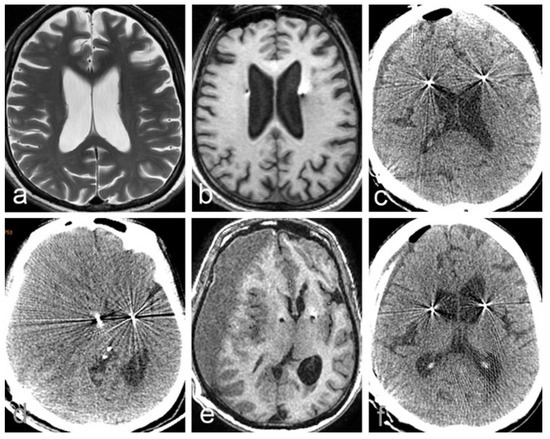

2.2. Case 2

| Case 2 | 56 | M | Alzheimer’s disease | fornix | Yes | Yes | 49 days | description | poor |